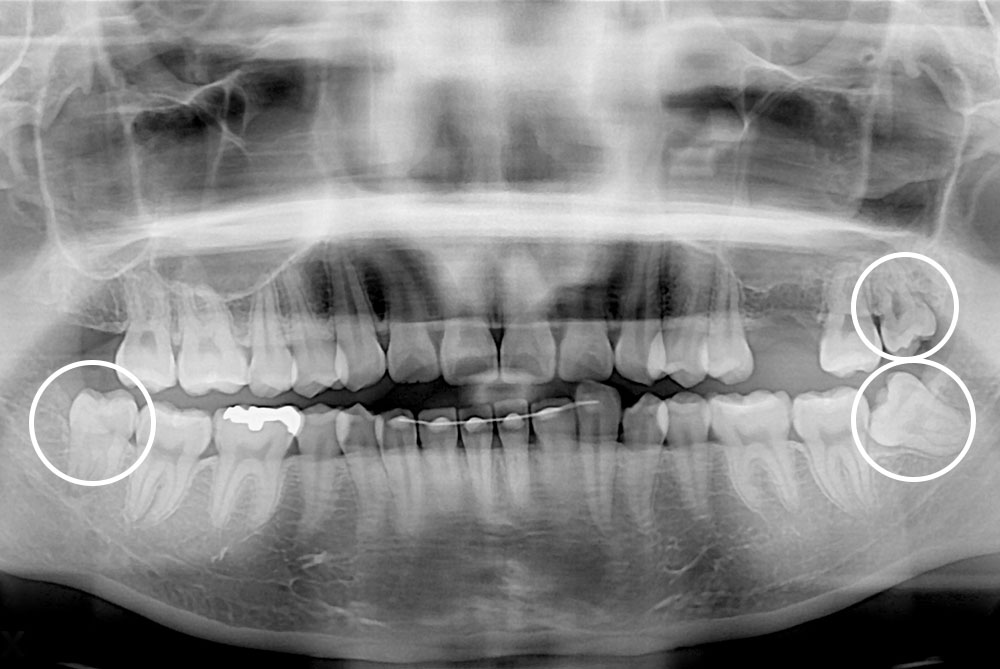

[사랑니] 매복 사랑니 발치

치료전 : 2018-07-31

치료후 : 2022-12-22

세종치과는 구강악안면외과학 박사이신 원장님이 발치하는 치과입니다.